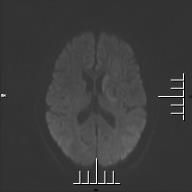

術(shù)前MR檢查示:左側(cè)基底節(jié)區(qū)腦梗死。